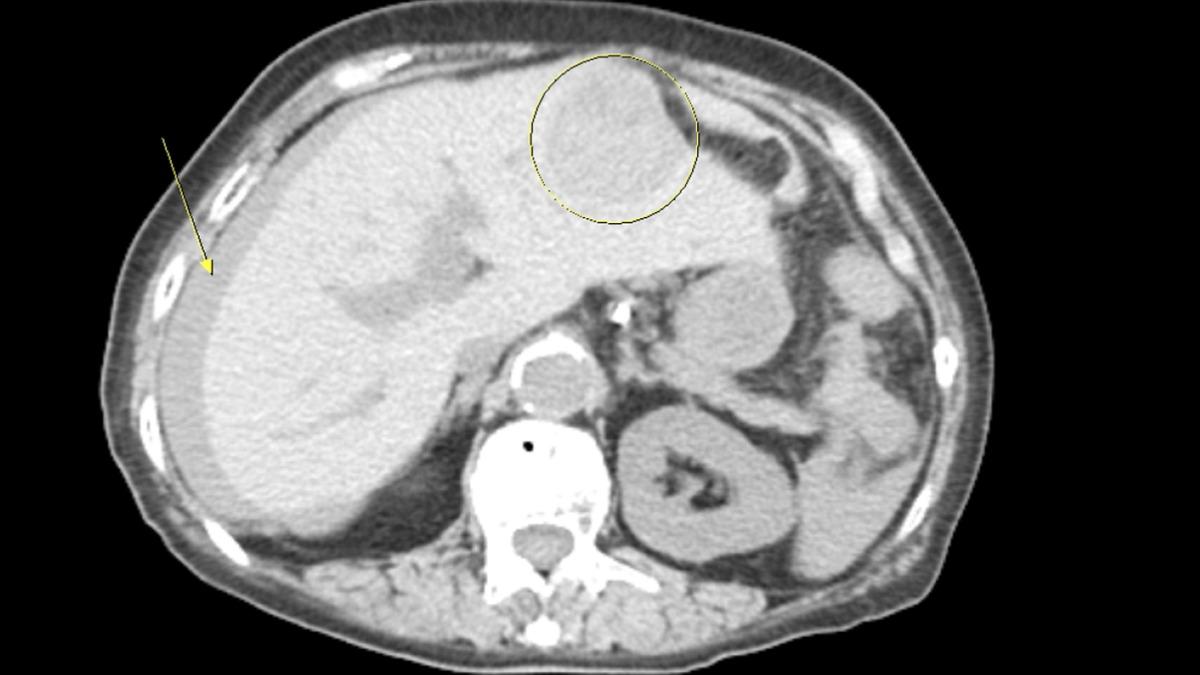

據了解,阿嬤過去並無肝癌就醫紀錄,但日前她遇上突發性腹痛,不過奇怪的是,阿嬤沒有外傷、嘔吐、拉肚子或發燒,原本以為只是單純肚子痛,但因為整整腹痛一天,家人保險起見帶阿嬤掛急診,經林俊男抽血、急診超音波檢查,發現阿嬤腹腔有積液情形,將成分抽出驚見10CC血液,研判是肝腫瘤破裂出血。

林俊男說明,每天在急診都遇到許多腹痛病患,但因為肝臟腫瘤起初不太會痛,所以很少有病患特別去做檢查,等到出現明顯徵兆後,往往都已經是中後期,現今可用急診超音波加速診斷及治療,避免在等待過程中,病患持續腹內出血,造成低血容性休克,更嚴重可能導致凝血功能異常、低體溫等惡性循環。同時林俊男進一步補充,肝癌破裂徵兆為急性腹痛、腹脹、貧血及低血容性休克,而肝癌在近10年來,一直是台灣癌症死亡的第二位,其中腫瘤破裂出血僅輸給腫瘤進展及肝衰竭,為第三大死因,致死率高達25至75%,是非常危險,且不算少見的狀況。